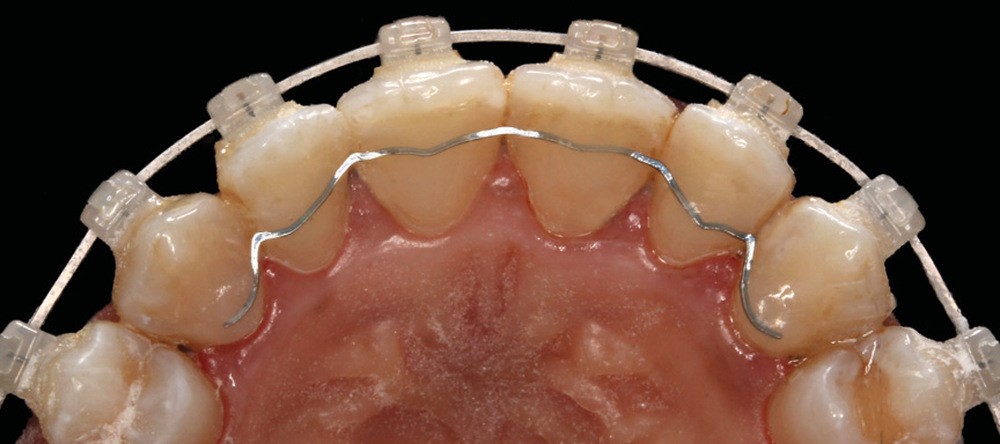

C’est à ces questions que nous permettront de répondre les deux premiers conférenciers, parodontologistes : le Dr Béatrice Straub nous présentera le renfort parodontal minéralisé, technique qu’elle a développée et pratique depuis de nombreuses années, pour éviter les préjudices des mouvements orthodontiques à risque, notamment lors des décompensations préchirurgicales (fig. 1a-d) ; le Pr Anton Sculean abordera le thème des greffes, avec leurs indications, les différentes techniques à privilégier et illustrera ses propos par de nombreux cas cliniques aux résultats esthétiques impressionnants.

Le début et milieu d’après-midi seront consacrés à l’empreinte numérique, désormais utilisée pour les empreintes d’étude, les set-up, le thermoformage. Les Drs Guillaume Lecocq et Stéphane Desplanques monteront le thermoformage et comment ces empreintes numériques peuvent permettre de confectionner des appareils vestibulaires, linguaux, voire des aligneurs (fig. 1 et 2).